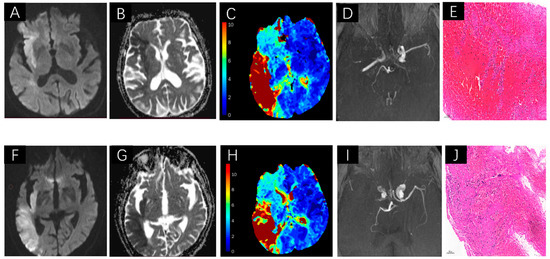

Figure 2.

A demonstration of thrombi measurements on DWI, ADC map, PWI, MRA and Histological images. A 81 year-old female patient. DWI demonstrates acute right MCA infarctions (A), hypointense in ADC map (B), hyperintense signal shows in Tmax > 6 s volume map (C), accompanied by MCA occlusion on MRA (D), Red blood cell-dominant thrombus on histological sections (E). A 83-year-old male patient. There are right hemisphere infarctions on DWI (F), and hypointense in ADC map (G), hyperintense signal shows in Tmax > 6 s volume map (H), accompanied by MCA occlusion on MRA (I), Fibrin-dominant thrombus on histological sections (J).